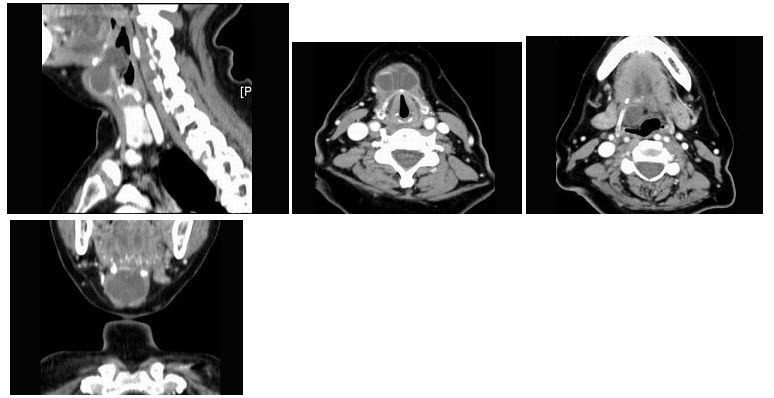

189、单项选择题

女性,28岁。2个月前发现右颈有一肿块,无压痛,可移动。肿块缓慢增大。患者有盗汗、红细胞沉降率加快。体检:右侧胸锁乳突肌后缘可触及串状肿大淋巴结,直径0.7~1.5cm。CT图像如下,可诊断为()

A.颈淋巴结结核

B.淋巴瘤

C.神经鞘瘤

D.转移瘤

E.淋巴管瘤